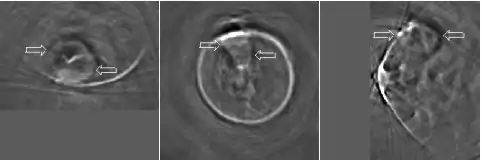

Thermoacoustic imaging was originally proposed by Theodore Bowen in 1981 as a strategy for studying the absorption properties of human tissue using virtually any kind of electromagnetic radiation.[1] But Alexander Graham Bell first reported the physical principle upon which thermoacoustic imaging is based a century earlier.[2] He observed that audible sound could be created by illuminating an intermittent beam of sunlight onto a rubber sheet. Shortly after Bowen's work was published, other researchers proposed methodology for thermoacoustic imaging using microwaves.[3] In 1994 researchers used an infrared laser to produce the first thermoacoustic images of near-infrared optical absorption in a tissue-mimicking phantom, albeit in two dimensions (2D).[4] In 1995 other researchers formulated a general reconstruction algorithm by which 2D thermoacoustic images could be computed from their "projections," i.e. thermoacoustic computed tomography (TCT).[5] By 1998 researchers at Indiana University Medical Center[6] extended TCT to 3D and employed pulsed microwaves to produce the first fully three-dimensional (3D) thermoacoustic images of biologic tissue [an excised lamb kidney (Fig. 1)].[7] The following year they created the first fully 3D thermoacoustic images of cancer in the human breast, again using pulsed microwaves (Fig. 2).[8] Since that time, thermoacoustic imaging has gained widespread popularity in research institutions worldwide.[9][10][11][12][13][14][15] As of 2008, three companies were developing commercial thermoacoustic imaging systems – Seno Medical,[16] Endra, Inc.[17] and OptoSonics, Inc.[18]

Microwaves have also been used to form 3D thermoacoustic images of the human breast. One of the first devices to do so is depicted in Fig. 10. It consisted of an array of eight waveguides, which directed microwave energy into the breast. A transducer array was rotated in synchrony with the waveguides in order to acquire sufficient data to reconstruct the internal structures of the breast. Figure 11 shows an animation of the typical glandular tissue pattern in a normal breast.

- ↑ Kruger RA, Miller KD, Reynolds HE, Kiser Jr WL, Reinecke DR, Kruger GA. Contrast enhancement of breast cancer in vivo using thermoacoustic CT at 434 MHz. Radiology 2000;216: 279-283.